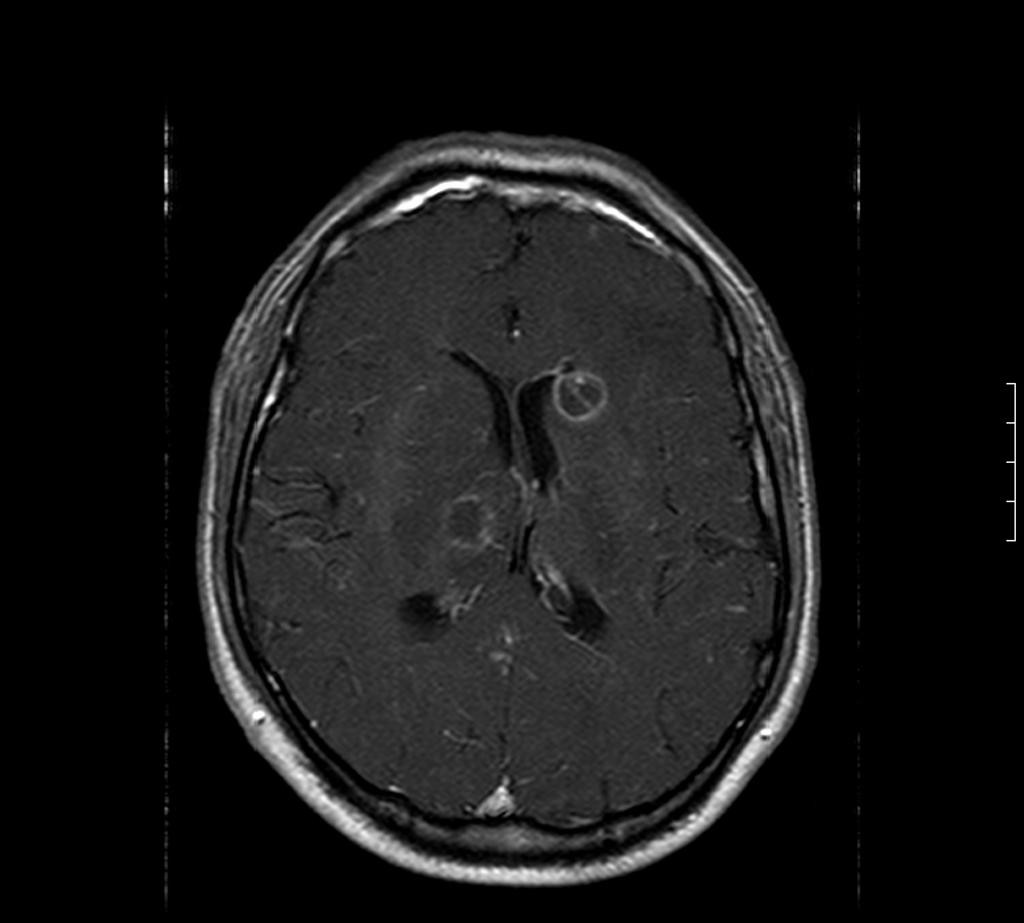

Toxoplasmose

• Toxoplasma gondii

• Bénigne chez l’immuno compétent

• Gravissime chez l’immuno déprimé

• Forme encéphalitique (fièvre, céphalées, confusion)

• Forme focale : déficit, comitialité

• Possibilité d’atteinte médullaire

• PL : lymphocytose modérée

IRM

• Forme pseudo-encéphalitique (rare)

• Forme nodulaire pseudo tumorale (fréquente)

• Lésion élémentaire

• Nodule hypoT1

• HyperT2

• Réhaussé en périphérie par le PDC

• Entouré d’œdème

• Lésions multiples disséminées sus et sous tentorielle

• Forme hémorragique classique notamment après traitement